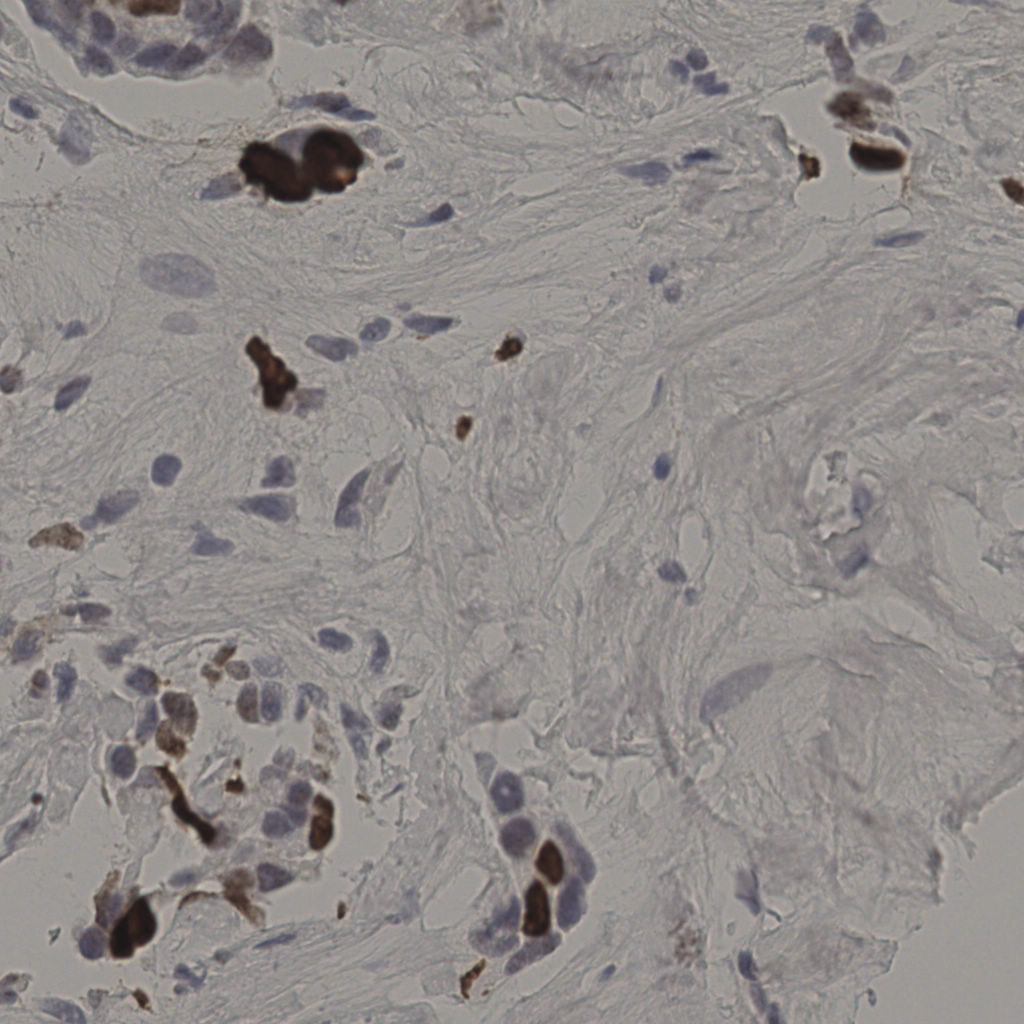

17.75%

Ki67 指数

阴 7986 阳 1723